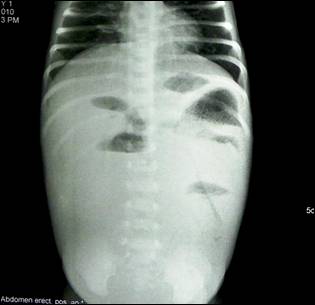

Image 1: Plain X-ray abdomen shows distal bowel obstruction.